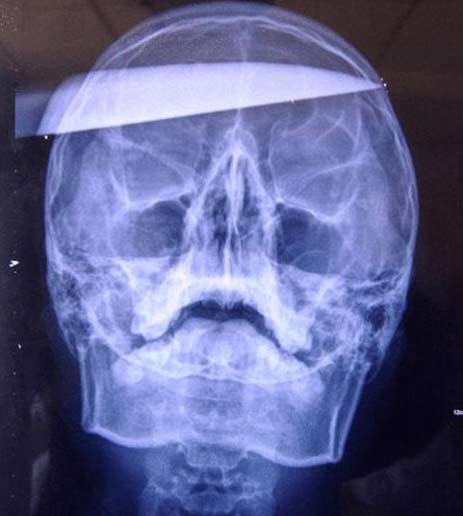

병원에 실려 갔을 당시 웨이의 왼쪽 두개골을 찌르고 들어간 25cm 길이의 식칼은 왼쪽에서는 손잡이만 보일 정도였고 두개골을 관통해 오른쪽에 식칼 끝부분이 튀어 나와 있었다. 식칼 제거수술을 한 제2지린대학병원의 얀시준 교수는 “그의 얼굴은 피로 범벅이 돼 있었지만 의식은 있는 상태였다”고 당시 상황을 전했다.

얀 교수는 “X레이 등으로 정밀 검사를 한 결과 대동맥이나 신경 등을 건드리지 않은 것으로 나타났다”며 “그러나 수술 후 감염이나 뇌 손상, 간질 증상 등의 후유증을 겪을 수 있다”고 말했다. 국민일보 쿠키뉴스 정민 기자 tazza@kmib.co.kr